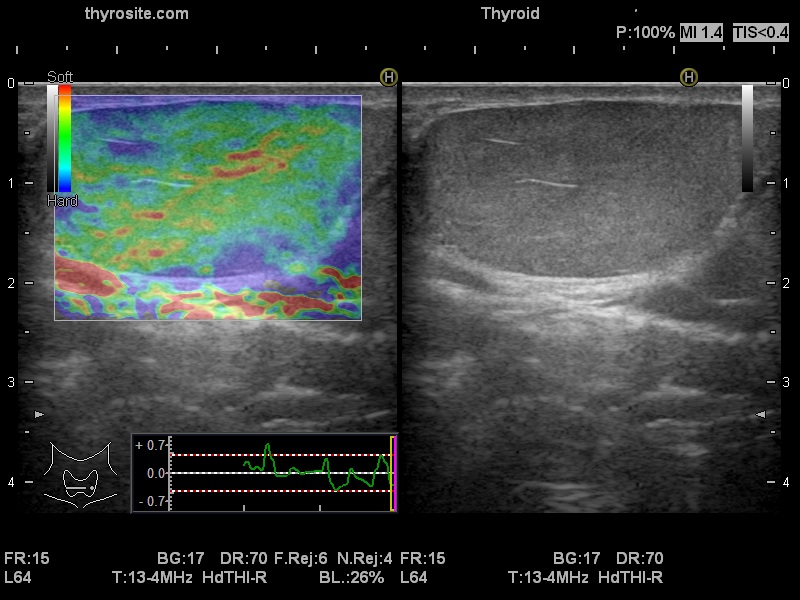

Elastography: A lipoma - case 916 (ultrasonographic picture 9)

Several centimeters under the thyroid in the middle of the neck, transverse scan, elastography. The mass proved to be harder than a usual case of a lipoma.